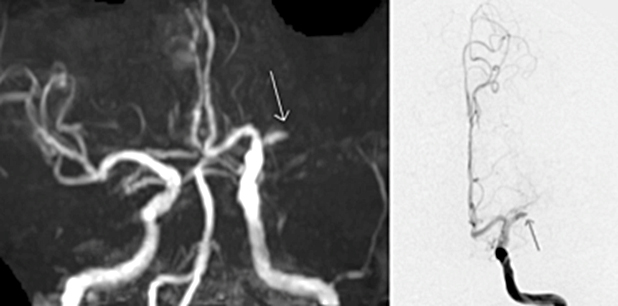

基本的に全身麻酔で治療を行います。足の付け根や肘にある太い動脈にカテーテルを入れて、レントゲンで確認しながら首や脳の詰まっている血管に移動させ、治療を行います。原則的には脳梗塞を起こしてから8時間以内の患者さんに行うことができますが、前に説明したように脳梗塞の範囲や側副血行の程度によっては24時間以内であれば行うことがあります。